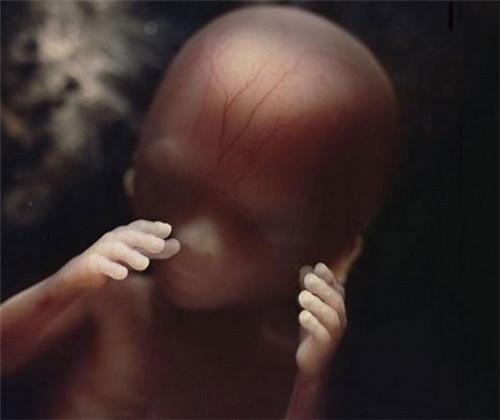

第10周。此时眼睑半闭,几周内会完全闭合

10周。胎儿已经可以使用双手来探索周围的环境

透过薄薄的皮肤,血管清晰可见.